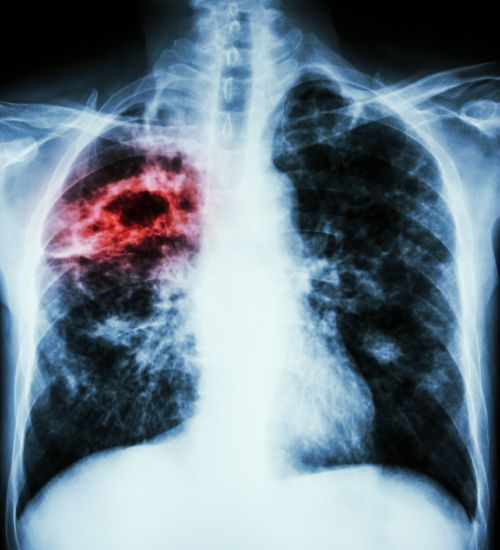

Application of FITC-Trehalose in Tuberculosis Diagnosis